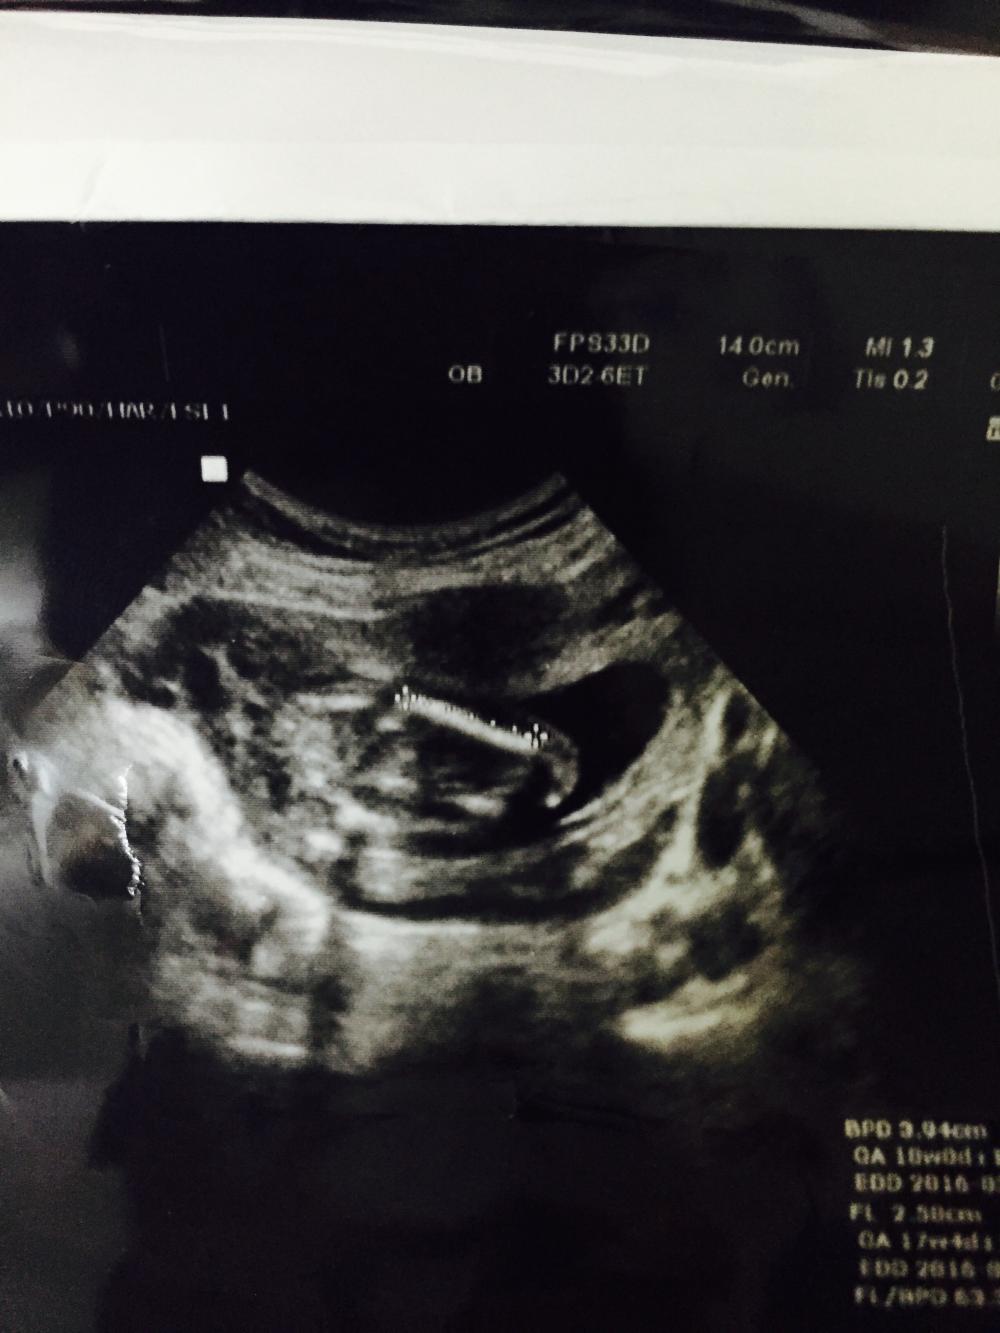

حبيبتي الله يفرحك بما تتمنى السونار في الشهر الخامس يكون واضح

واضح ولا ارجع ارسل لانها كذا وحده